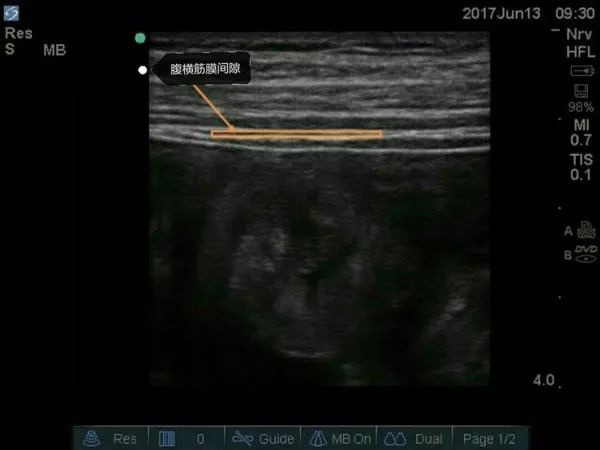

超声引导下腹横平面TAP阻滞要点

①适应证: 剖腹手术、阑尾切除术、腹腔镜手术、剖宫产术后镇痛。

②探头位置: 横向放置在肋缘和髂棘之间腋前线处的腹壁。

③目标: 局麻药在腹横肌和腹内斜肌之间扩散。

④局麻药: 每侧0.25%罗哌卡因20-30ml。

超声下孕妇的腹横筋膜图像